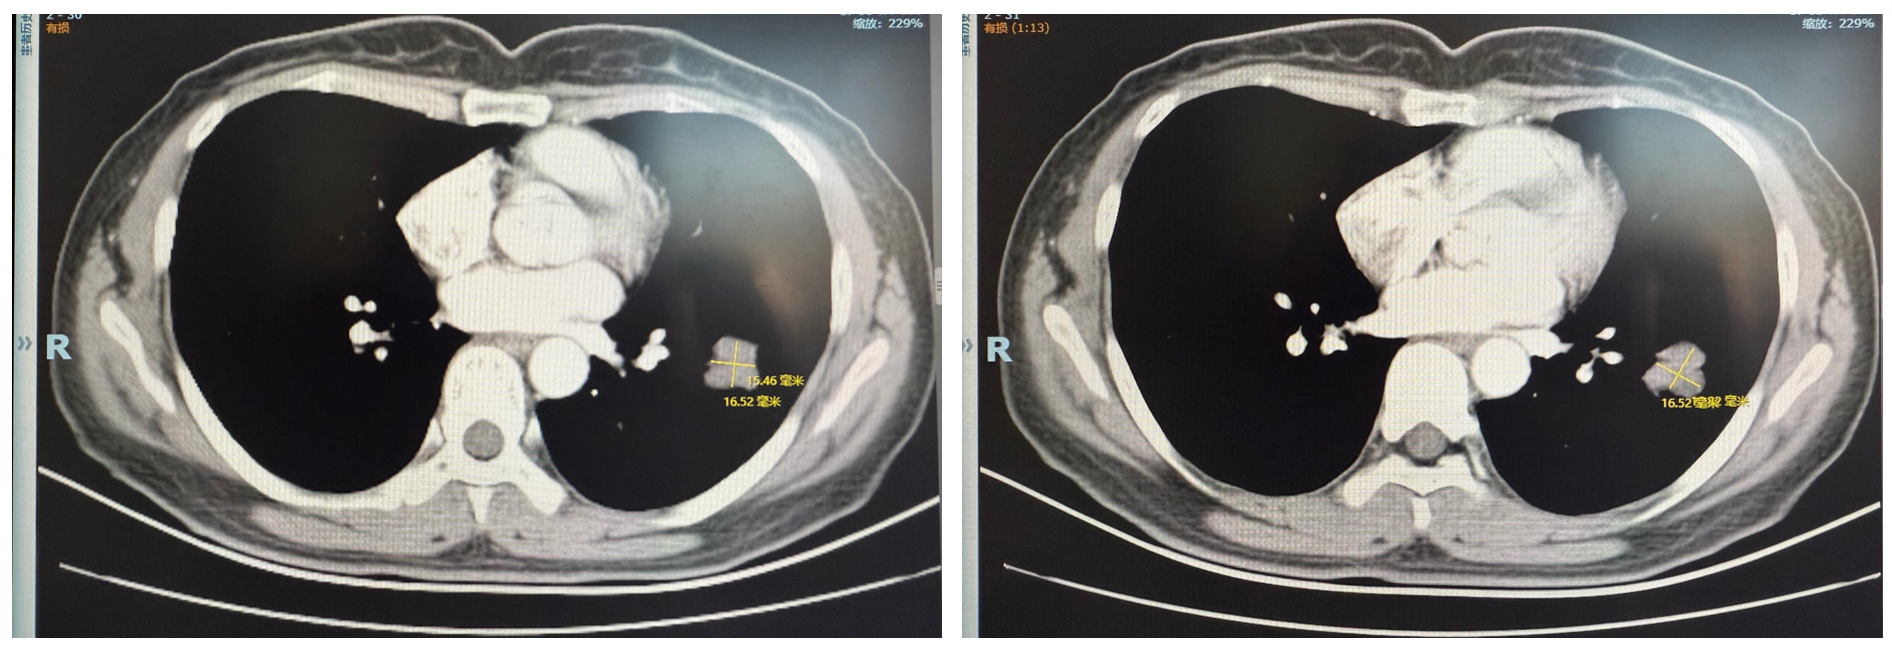

胸部强化CT(2025年6月20日):左肺下叶可见不规则肿块,大小约59×45mm,不均匀强化,边界清楚,周围见斑片;右肺尖见微结节、钙化灶及斑索。双侧胸膜未见增厚,未见胸水。纵隔内未见增大淋巴结。

图1 2025年6月20日CT图像